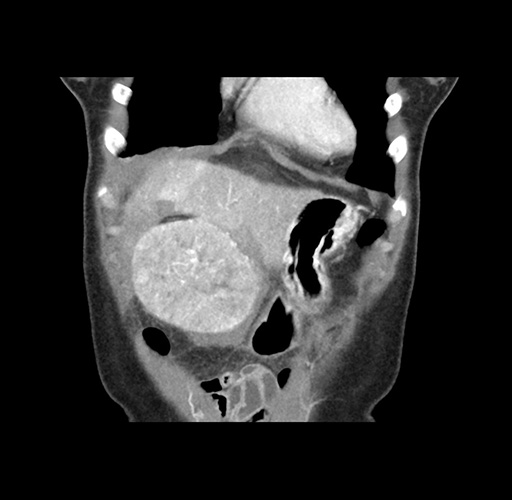

Imaging Analysis

Look through the patient's CT scan to identify any areas of concern for the necessary procedure.

Based on your CT findings, which issue(s) would give reason for "planned slowing down moment(s)" in this case?